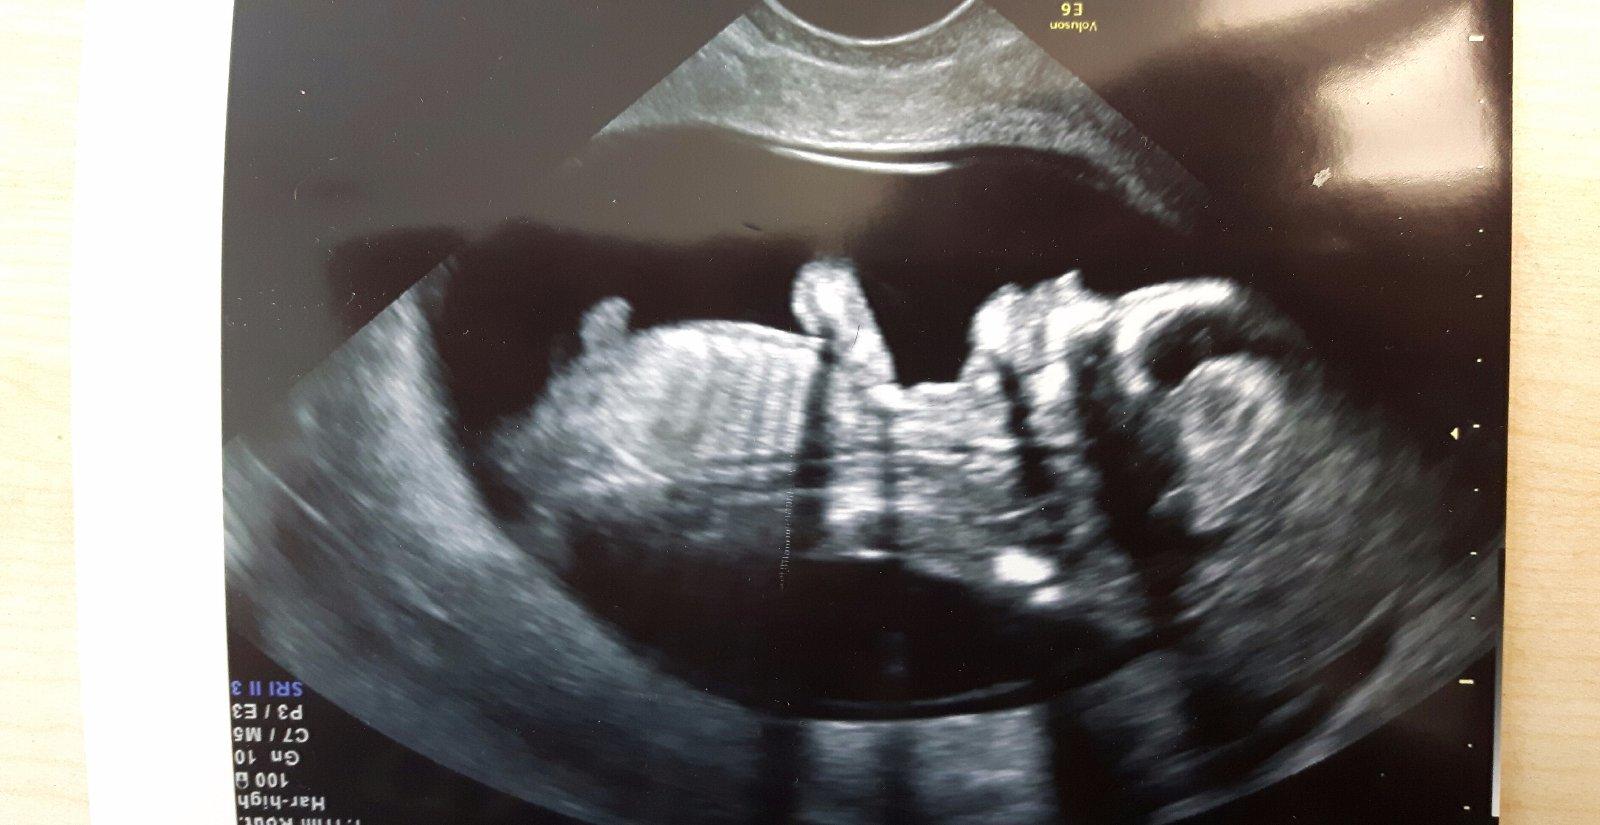

Ahoj maminky a budoucí maminky 😉 Prosím, poradila byste mi některá, co vidíte na fotce z ultrazvuku ve 20. týdnu za pohlaví? Určitě jste foteček viděly už mraky, proto vás žádám o radu...Nechci nikoho ovlivnit, proto svůj tip řeknu později 🙂 Děkuju moc!!!

Prosím jestli ještě jsem na tuto diskuzi chodí. Co může být toto za pohlaví?; poradí někdo?

Ahoj holky, co myslite, vyctete neco z tohoto obrazku? Holka nebo kluk? 😉😉

Je tu neco videt? Kde vidite ty hrbolky? 🙂 omlouvam se za dotaz blbecka, ale ja dokud jsem u prvniho nevidela sourek a pindika, nevidela jsem nic. 😀. Tady je neco videt?

Holky, nevidíte naaahodou?

Ahoj holky muzete my taky potvrdit ze cekam chlapecka moc jsem chtela holcicku mam uz dva chlapecky doma dekuji 🙂